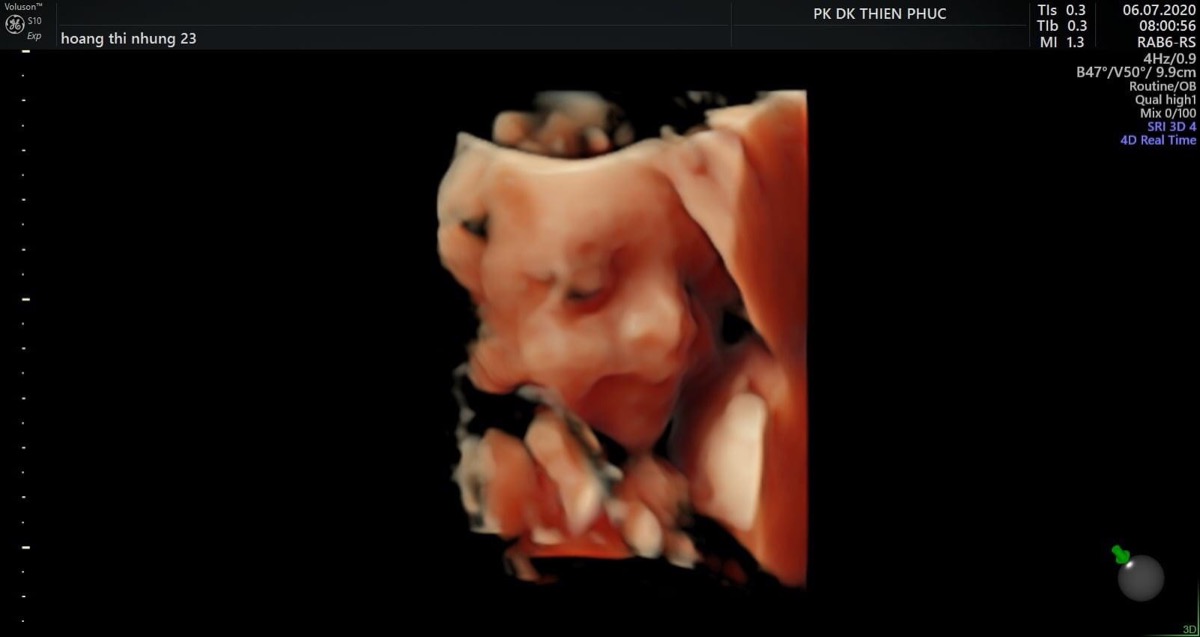

Nay đi thăm con 25w2d mà bé nhà em mới 718gr. Em vẫn ăn uống đều đặn,uống thêm ngũ cốc các loại hạt mà con vẫn nhỏ quá 😓 Em thì tăng 6kg ròi,mom nào có cách giúp bé tăng cân hơn không ạ